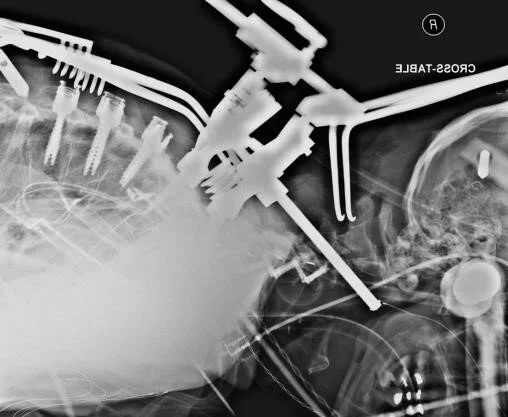

In the second stage of the procedure, Drs. Bennett and McEntarfer did laminectomies at C7 and T1 and hemilaminectomies at C6 and T2 to allow for visualization of the spinal cord. The team then proceeded with the T1 PSO utilizing the Reline 3CO rack and closely monitoring motors with NVM5, allowing them to move efficiently through the steps and bilaterally close the osteotomy to restore sagittal alignment. Bendini was utilized for bending the rod. This time-saving technology facilitated a precise bend in the rod allowing the rack compressors to close the osteotomy and minimized the need for additional reduction.

Bennett-2.jpeg

Intraoperative navigation and NuVasive Power were a benefit for this procedure in multiple ways. When completing the PSO, navigated instruments facilitated an accurate anterior depth for bony removal. Navigating pedicle screws at C7 and in the upper thoracic spine allowed for excellent fixation across the osteotomy site and utilizing power effectively-balanced speed and maneuverability. Many PSOs will utilize a quad-rod technique across an osteotomy site. With a smaller Reline pedicle screw utilized at C7, a transition rod was placed to allow the 5.5 mm diameter rod to cross the osteotomy and eliminate the need for supplemental hardware.

“Several key technologies were used in this case. I placed my C7 and thoracic pedicle screws under power and with navigation. The use of power minimizes deflection and maximizes navigation accuracy by minimizing force applied to the spine. Additionally, the drill rotates completely coaxially with the screw and minimizes off-axis precession. Navigation is also very useful for guiding the depth and extent of the osteotomy as well as any necessary rib resections. Finally, there are several great tools in the 3CO set. In particular, I feel the posterior wall pusher is more effective than using a tamp or down-going curette, and using the rack-compressor across the C7 and T2 screws enables local angulation across the osteotomy when manipulating the Mayfield.”